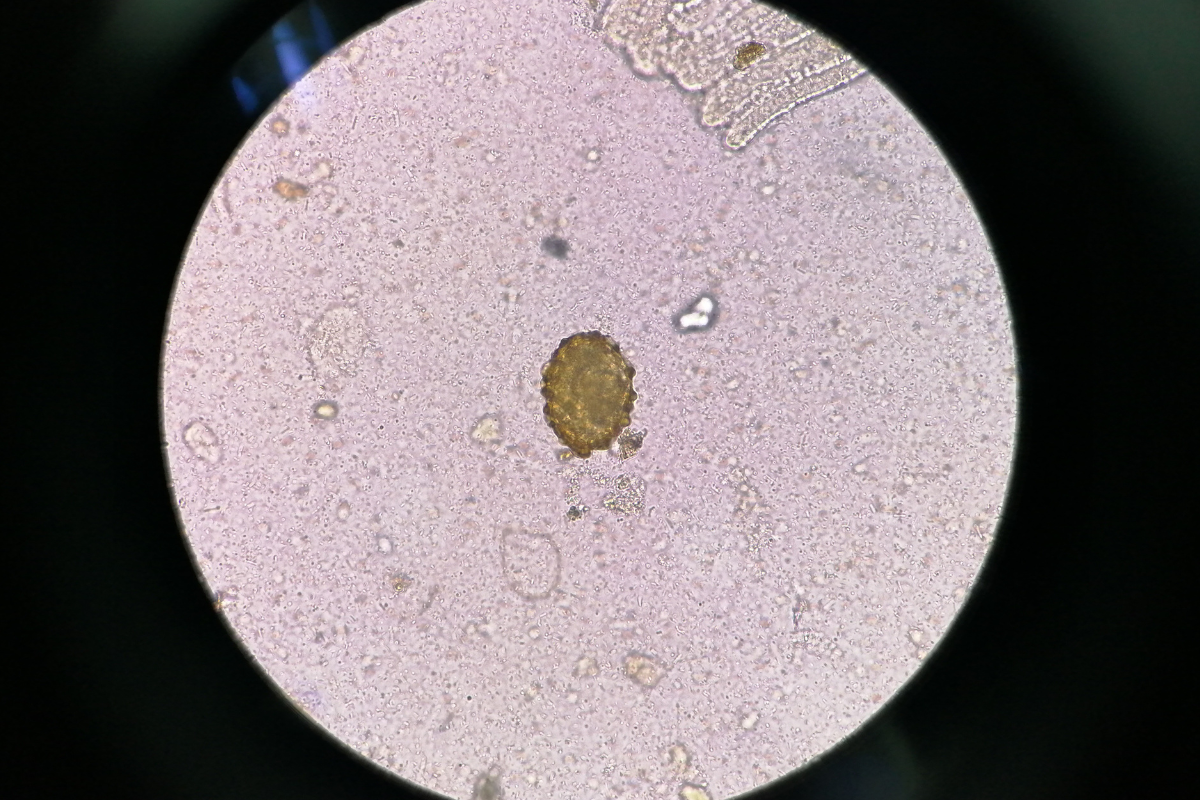

Treating Parasites with Oxygen Therapies

In this post, I will discuss common oxygen therapies and share which one I believe is the most economical and effective one for treating parasites. This training is for educational purposes only. It is not intended to replace the necessary measures of a healthcare professional. Oxidizing agents can be very corrosive and cause tissue damage